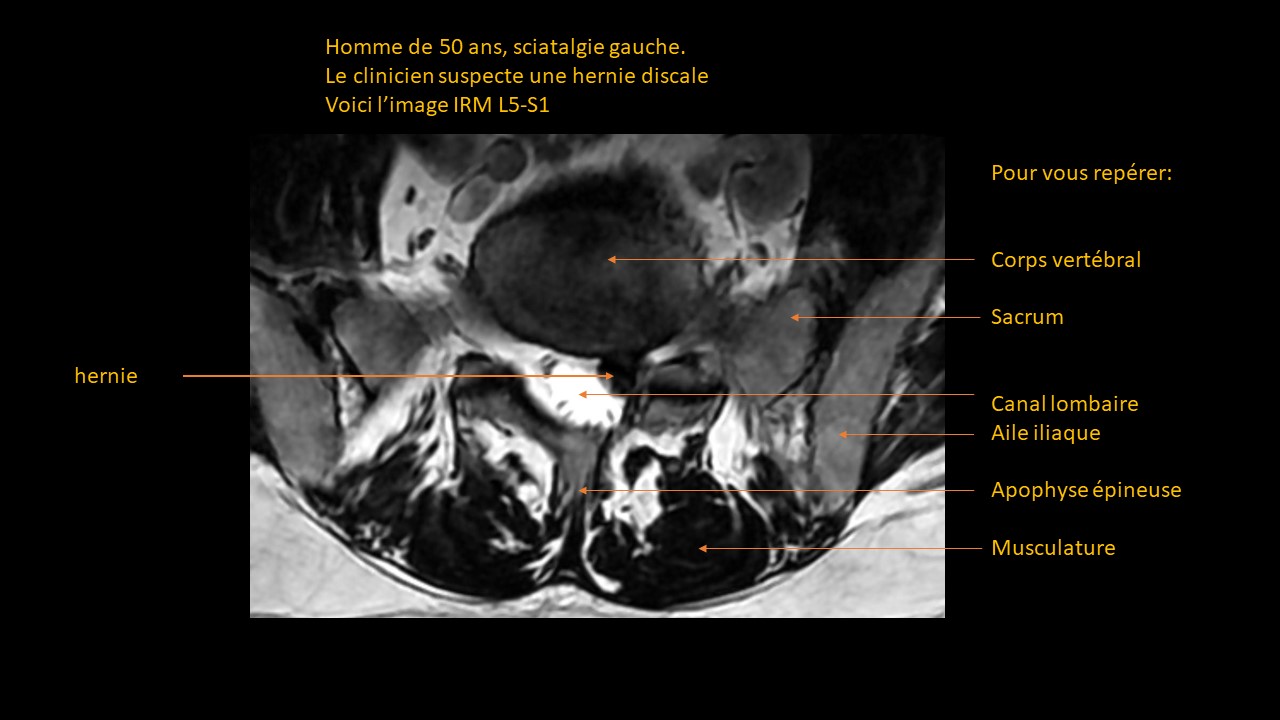

Formation continue sous forme de vignettes ( Quiz )